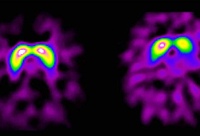

Die Abbildung zeigt rechts eine gesunde Kontrollperson und links einen Patienten mit rechtsbetonter Parkinsonkrankheit. Beim Parkinsonpatienten findet sich eine geringere Anreicherung des Signals links. (Foto: Medizinische Universität Innsbruck)

Und da stützen sich viele Ärzte auf die Bildgebung: In mehreren Studien wurden die Möglichkeiten bestätigt, mit Ultraschall die Entwicklung der Krankheit vorher zu sagen. In Zukunft sollen Risikomarker viel genauer und viel früher mögliche Betroffene erkennen.